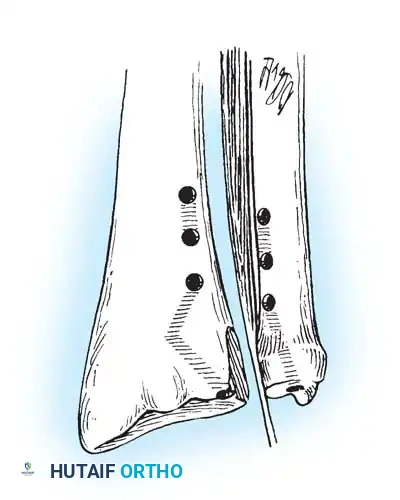

Preparation of the distal ulna: Drill holes are created at the fovea to facilitate transosseous suture passage for anatomic TFCC reattachment.

Transosseous Repair Technique:

1. Identify the foveal detachment arthroscopically or via an open dorsal ulnar approach.

2. Prepare the ulnar fovea down to bleeding bone using a burr or curette to stimulate a healing response.

3. Utilize a targeting guide to drill two converging osseous tunnels from the ulnar neck into the fovea.